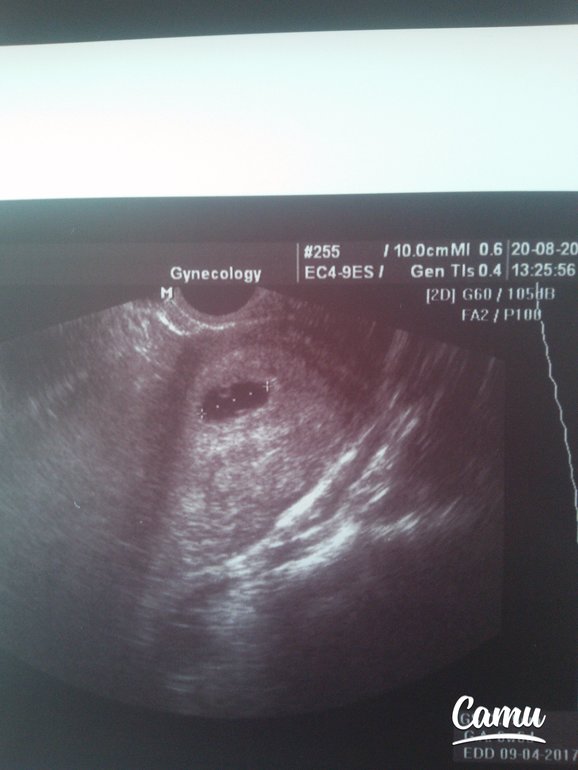

Врач собирает анамнез для уточнения наличия противопоказаний к проведению процедуры. Делает УЗИ для определения срока беременности. Берет анализы мазка на флору, группы крови и резус фактора. На первом приеме гинеколог подробно расскажет о том, как будет проходить медикаментозный аборт, какие ощущения могут быть и какие осложнения могут возникнуть. Для окончательного принятия решения, врач отпускает вас домой на 48 часов подумать.

4.Контроль УЗИ после аборта.

Через 10- 14 дней назначается проведение контрольного УЗИ после аборта. УЗИ проводят вагинальным датчиком- оценивают содержимое полости матки. К этому времени в нем должны отсутствовать элементы плодного яйца и сгустки крови. В этом случае аборт считается завершенным. Для восстановления организма женщины после аборта на 3 месяца выписываются гормональные контрацептивы.

Для выполнения УЗИ на раннем сроке должны быть показания. Основная цель —установить маточную локализацию плодного яйца: маточная, внематочная; вторая цель — определить жизнеспособность плодного яйца. Анатомия и все остальное — уже ближе к первому скринингу в 11-14 недель, но УЗИ в ранние сроки в основном преследуют эти две цели. По определенным ультразвуковым параметрам их возможно сделать.